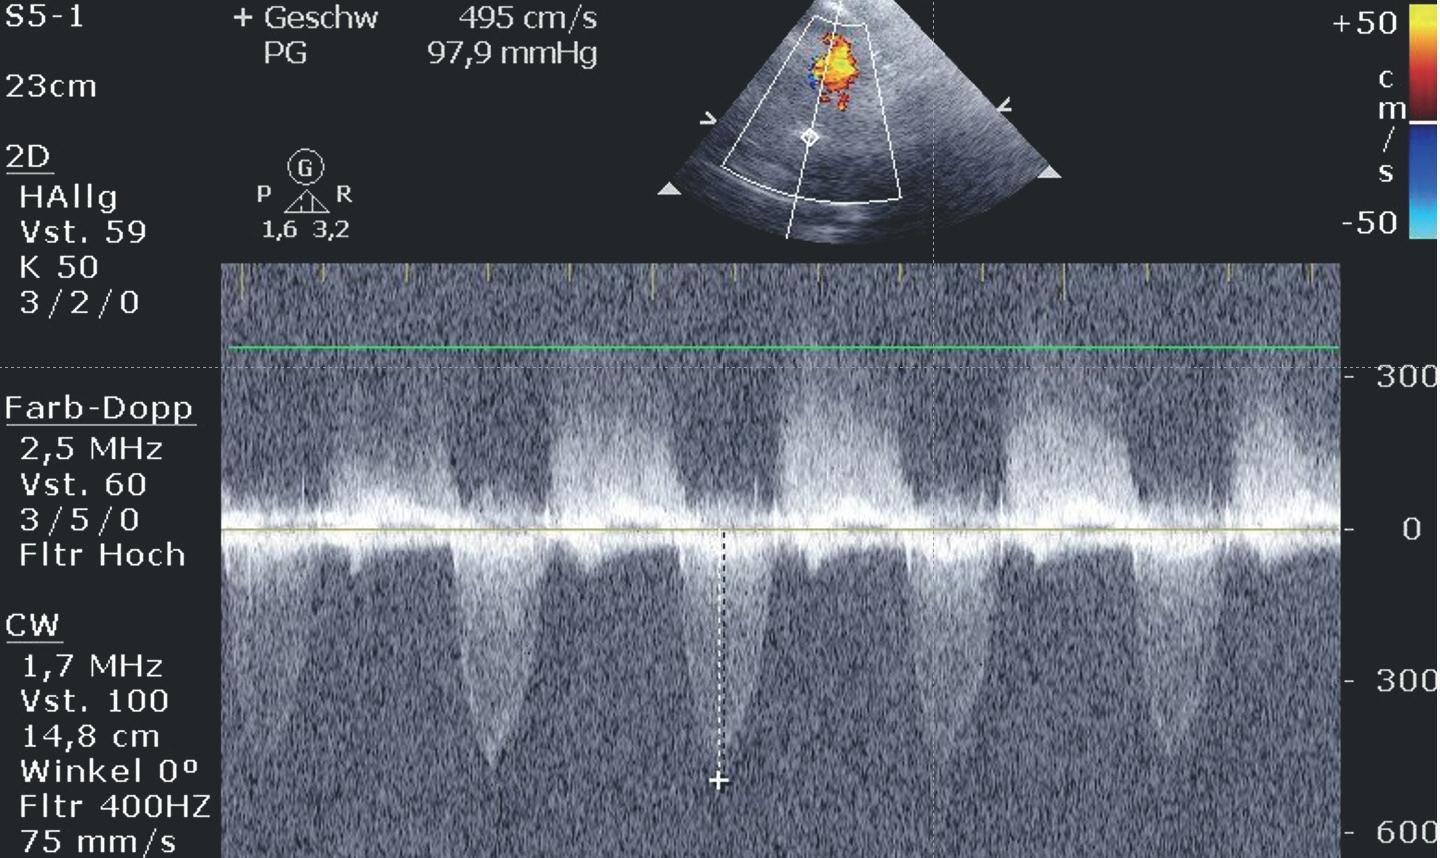

Abbildung 2: Über die Trikuspidalinsuffizienz kann der systolische PA-Druck im kleinen Kreislauf eingeschätzt werden. © zVg